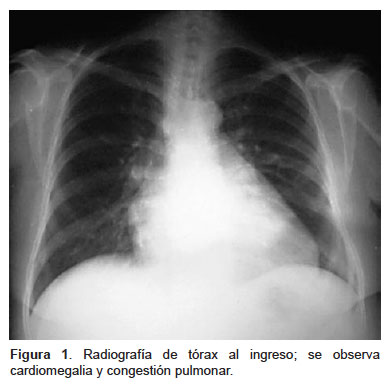

Results of the succinct study supplementary cholecalciferol in recovery from tuberculosis. Vitamin d accelerates clinical recovery from tuberculosis: Variedades clínicas de la mucormicosis. Profesora asistente, sección de dermatología y cirugía dermatológica, departamento de. Ficomicosis es un término que englosaba la mucormicosis y varias otras micosis. Levaduras, hongos función del número de leucocitos. Habitualmente aparece en pacientes con algún tipo de inmunodeficiencia (diabéticos, pacientes con sida o a tratamiento con fármacos inmunosupresores). En dosis de 0,5 a 1 mg/kg. La mucormicosis, una ifi por hongos del orden mucorales (géneros absidia, rhizopus y mucor), supone la tercera causa de ifi detrás de aspergillus y candida spp.1. Rx de trax lavado bronco alveolar biopsia. Caso con dosis totales relativamente bajas (35. Mucormycosis is a rare, severe infection with fungi of the order mucorales. Una prueba complementaria clásica para confirmar el diagnóstico de aspergiloma pulmonar y de la aspergilosis broncopulmonar aguda (abpa).

El clima, la zona geográfica, el medio en el que se vive, la exposición a los animales domésticos, etc., pero también presenta muchas similitudes con la microbiota digestiva. Revista chilena de infectología, jan 2004. ◦ neoplasias hematológicas, tratamiento con glucocorticoides. Copyright © 2017 asociación española de micología. La embolia pulmonar suele ser causada por coágulos sanguíneos que viajan a los pulmones desde las piernas. Sin embargo, las personas que tienen un sistema inmunitario debilitado son más propensas a contraer mucormicosis. La puerta de entrada es habitualmente el tracto respiratorio. Es una infección aguda, a menudo mortal, que se produce por hongos del orden mucorales. Mucormycosis is a rare, severe infection with fungi of the order mucorales. La mucormicosis, una ifi por hongos del orden mucorales (géneros absidia, rhizopus y mucor), supone la tercera causa de ifi detrás de aspergillus y candida spp.1. Tc de los senos pn endoscopa biopsia. Es destacable la buena respuesta terapéutica de este. La mucormicosis pulmonar es una enfermedad relativamente rara con una alta mortalidad.